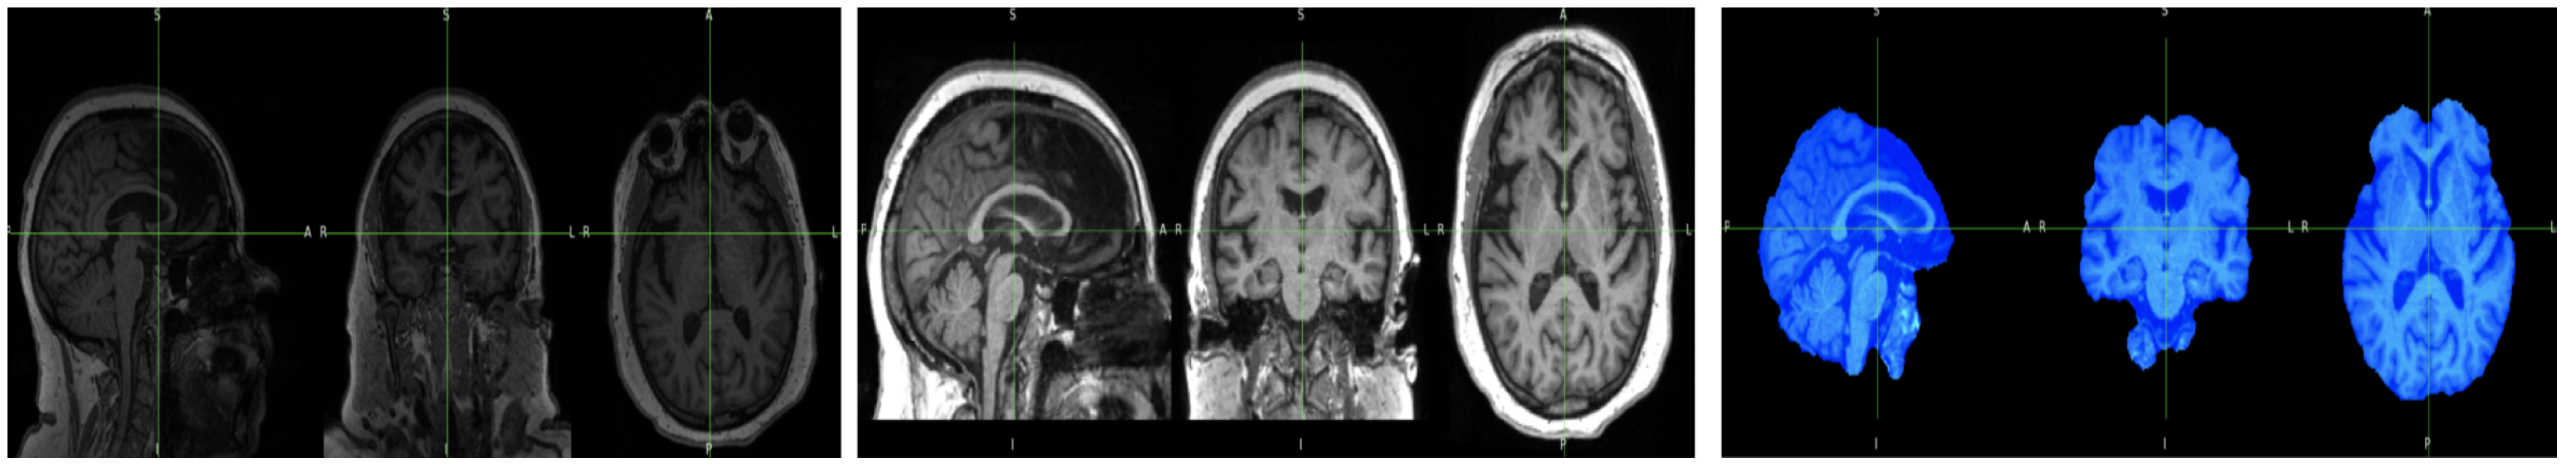

3.3. Dataset Collection

3.4. Dataset Preprocessing